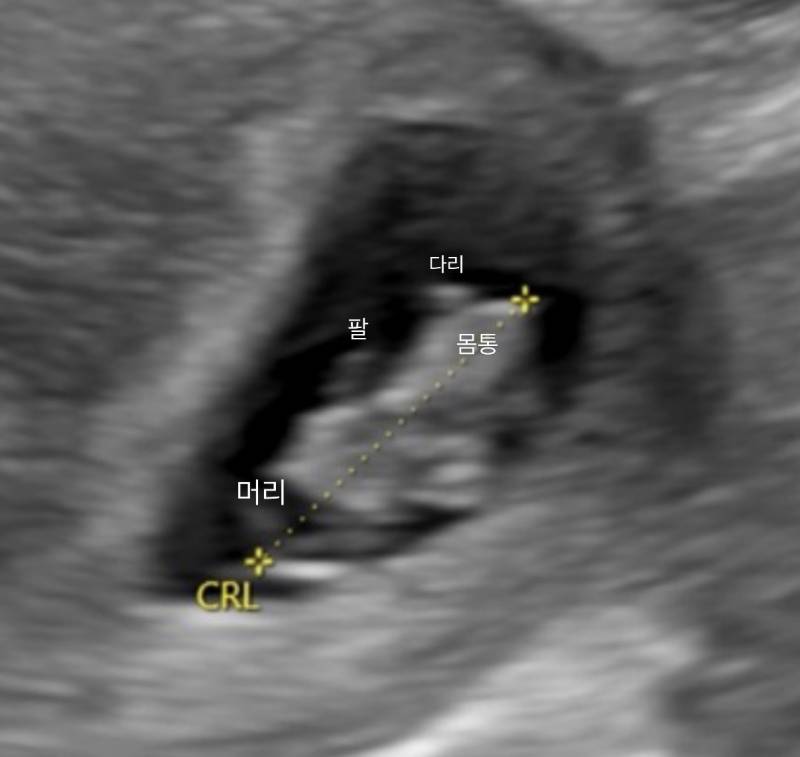

나 뱃속에 2센치짜리 아기있다 작성자 정보 신비한달15 작성 작성일 2026.04.15 13:00 컨텐츠 정보 80 조회 목록 답글 쓰기 본문 출처 https://www.instiz.net/name/66117114 63 너무.. 귀엽지....... 관련자료 이전 나영석 사단 제작진들은 방송 노출 엄청 하네요 작성일 2026.04.15 13:01 다음 갈수록 점점 커지는 목포 대왕돈까스집 작성일 2026.04.15 12:59 댓글 0 등록된 댓글이 없습니다. Select File Upload File 목록 답글 쓰기